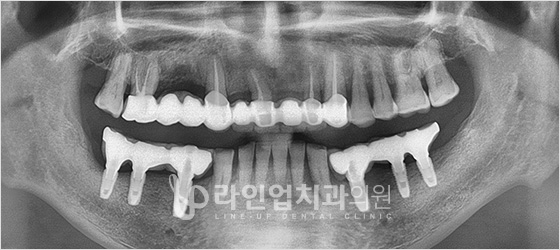

Before

After

Upper molars implant